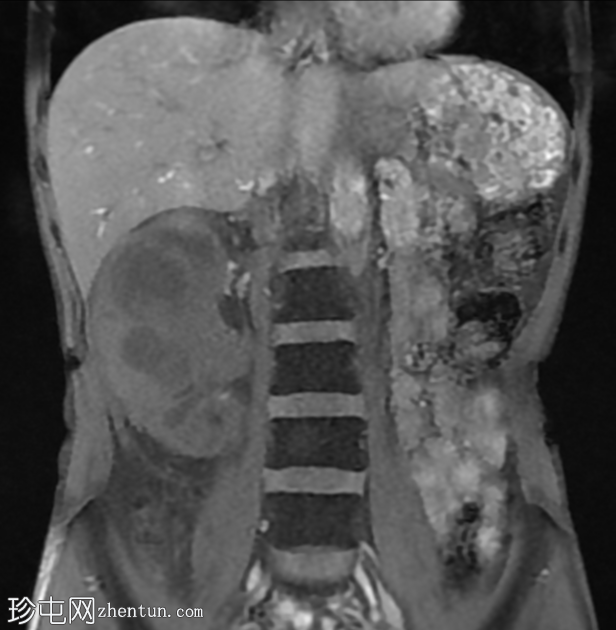

CT

轴位

平扫

冠状位

右肾前部可见一边界清晰的外生性病变,呈异质性,包含实性及囊性成分,内部可见多发结石。肾周可见模糊影。

左肾体积缩小且萎缩,可见多发结石。

病变内部存在结石及肾周模糊影提示炎症性病变,可能为局灶性黄色肉芽肿性肾盂肾炎(XGP),而非肿瘤性肿块(肾细胞癌)。